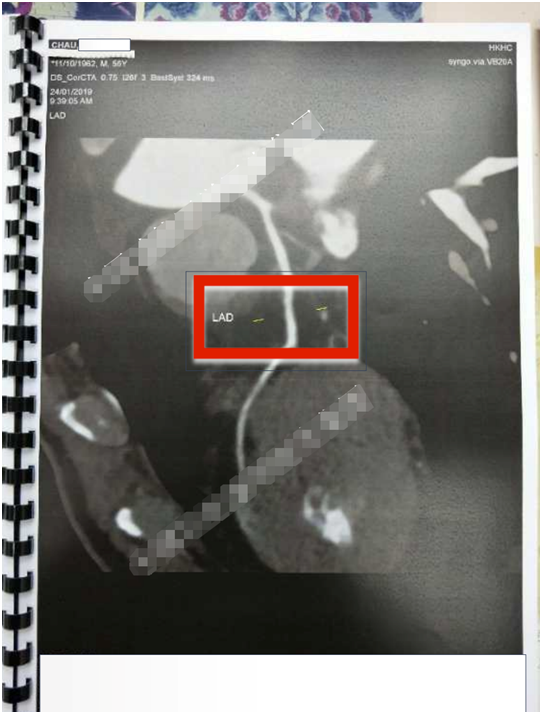

功能医学治疗第三步:功能医学干预后复查。

冠状动脉粥样硬化斑块消失、胸闷、胸痛消失。

2019年1⽉24⽇,冠状动脉造影:未⻅动脉斑块。